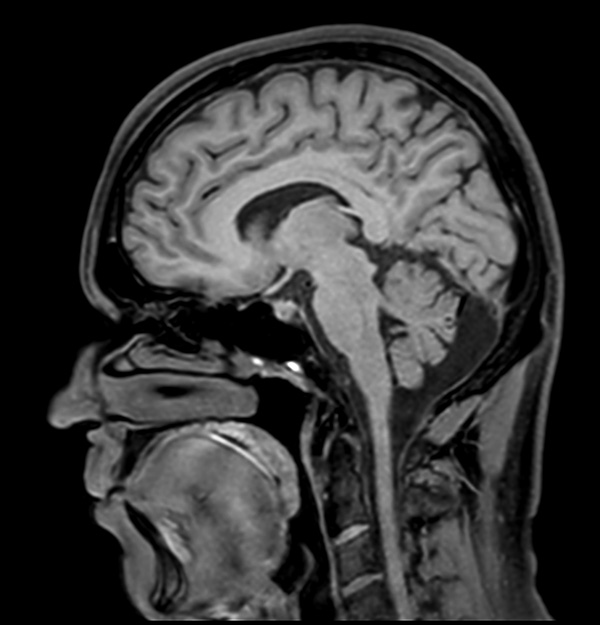

Comprehensive Brain imaging at 1.5T

Used Solution